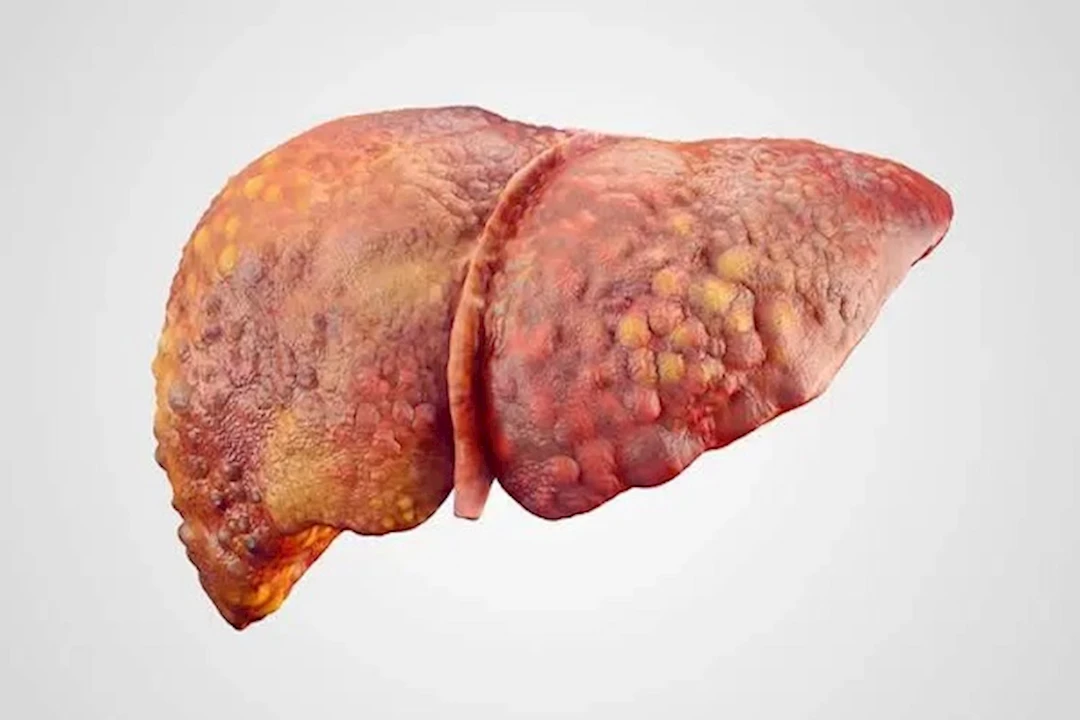

تليف الكبد مشكلة صحية خطيرة، يجب التعامل معها على الفور، وذلك لأن تركها دون علاج يهدد حياتك، حيث يتحول النسيج السليم للكبد إلى نسيج ندبي أو تليف، ما يعيق تدفق الدم عبر الكبد ويؤثر على وظائفه الحيوية.

وقدم موقع هيلث لاين، 7 علامات مبكرة يمكن أن تكشف تليف الكبد، من المهم التعرف عليها، من أجل سرعة العلاج، وتجنب المضاعفات الخطيرة.